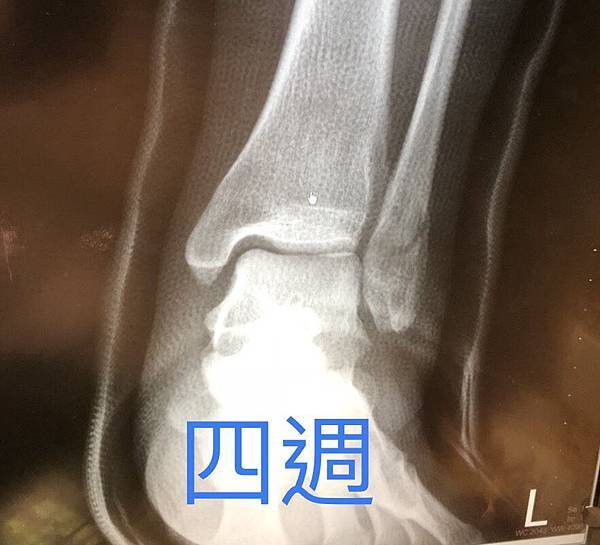

因此,吃兩個禮拜水藥的效果,連放三張讓大家比較,從上到下分別是受傷當天、沒吃藥兩周、吃藥兩周

第四周的照片,靠中心的裂痕明顯糊掉,看來進展不錯